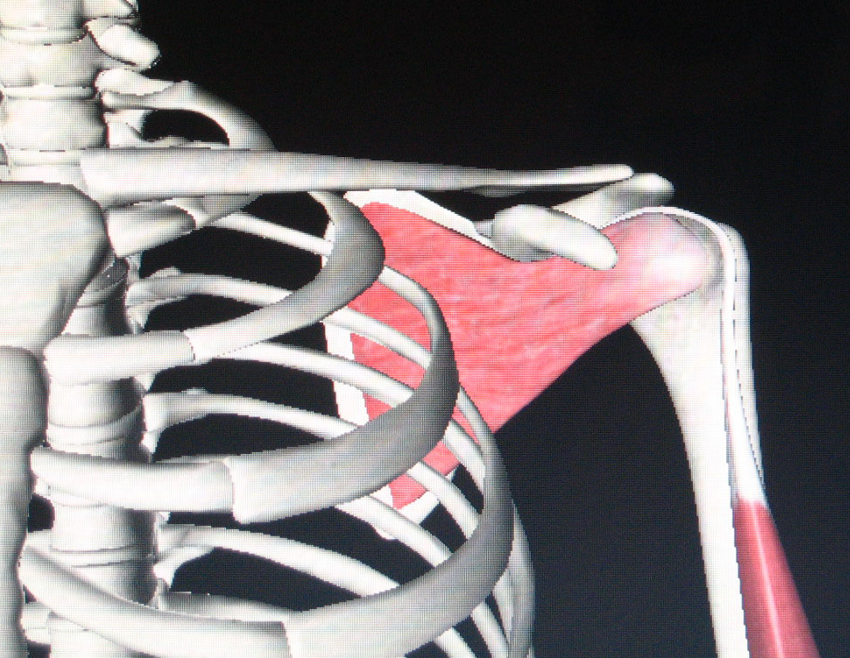

肱骨干上端解剖特点

肱骨头的关节面呈半圆形,朝上、内、后。正常肱骨头与肱骨干之间有140-180度的内倾角和15度的后倾角。

在肱骨头的关节面的边缘与肱骨结节之间有一浅沟,即解剖颈。外科颈相当于圆形的骨干与两结节交接处,此处的皮质突然变薄,为骨折好发处。

大结节及大结节嵴肌肉附丽(主要有4块)

小结节及小结节嵴肌肉附丽主要有3条

肱骨头的血供

肱骨头主要血供从前外侧进入,为旋肱前动脉的分支,相当于一般外科颈骨折部位的上方,此外尚有发自旋肱后动脉的后内侧动脉分支供应。肱骨头血供很好,一般骨折易愈合